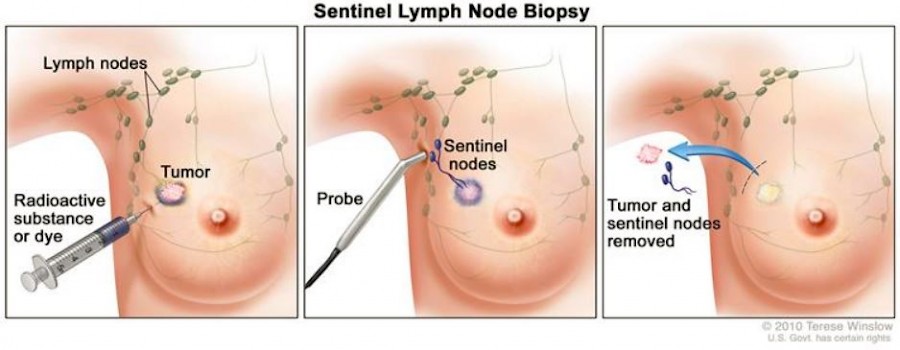

Kapitel 7: Operation, Biopsie und histologische Untersuchung - - - Kapitel 8: Gammasonden zur intraoperativen Lokalisierung - - - Kapitel 9: Strahlenschutz - - - Kapitel 10: Diagnostische Bedeutung - - - Kapitel 11: Andere SLN-Verfahren